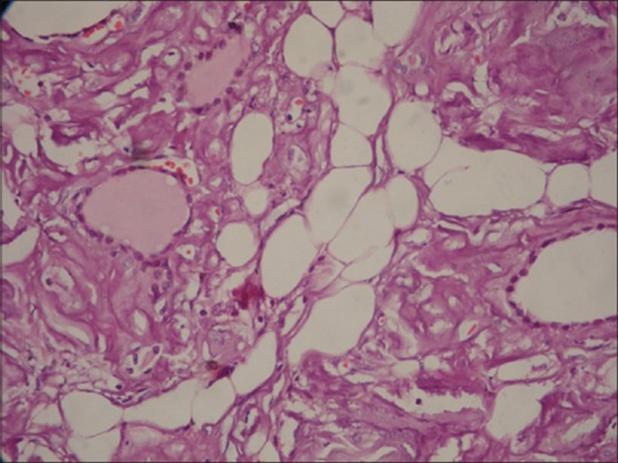

患者存在大量结节,行甲状腺全切除术。病理可见:右叶为12cm×7.5cm×7cm,左叶为9.6cm×6cm×5cm,包膜完整。在右叶切片中,发现一个4cm×3cm大小的部分囊性结节,边界清。左叶可见1个4cm×4cm大小的囊性结节。周围甲状腺组织硬化,呈浅棕色,外观均匀。镜检内含胶状物质的甲状腺滤泡增大、延长,滤泡及血管周围广泛聚集嗜酸性、无结构、不定形的淀粉样物质,滤泡和血管周围可见淀粉样物质积聚(见图1)。结晶紫染色切片可见甲状腺滤泡和血管之间弥漫性异染物质(见图2)。